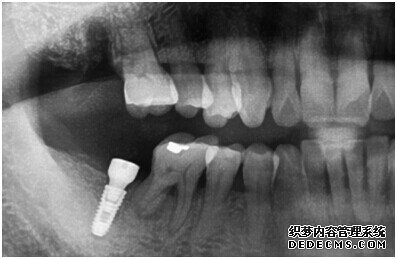

由CT片检查来看,刘女士口腔健康环境还是很好的,牙槽骨也适合种植牙的条件,而且由我们最后一颗牙是非常重要的,经过专家的建议和详细解释了原因之后,刘女士选择了美国百康种植牙。

种植体成功植入后的CT效果图